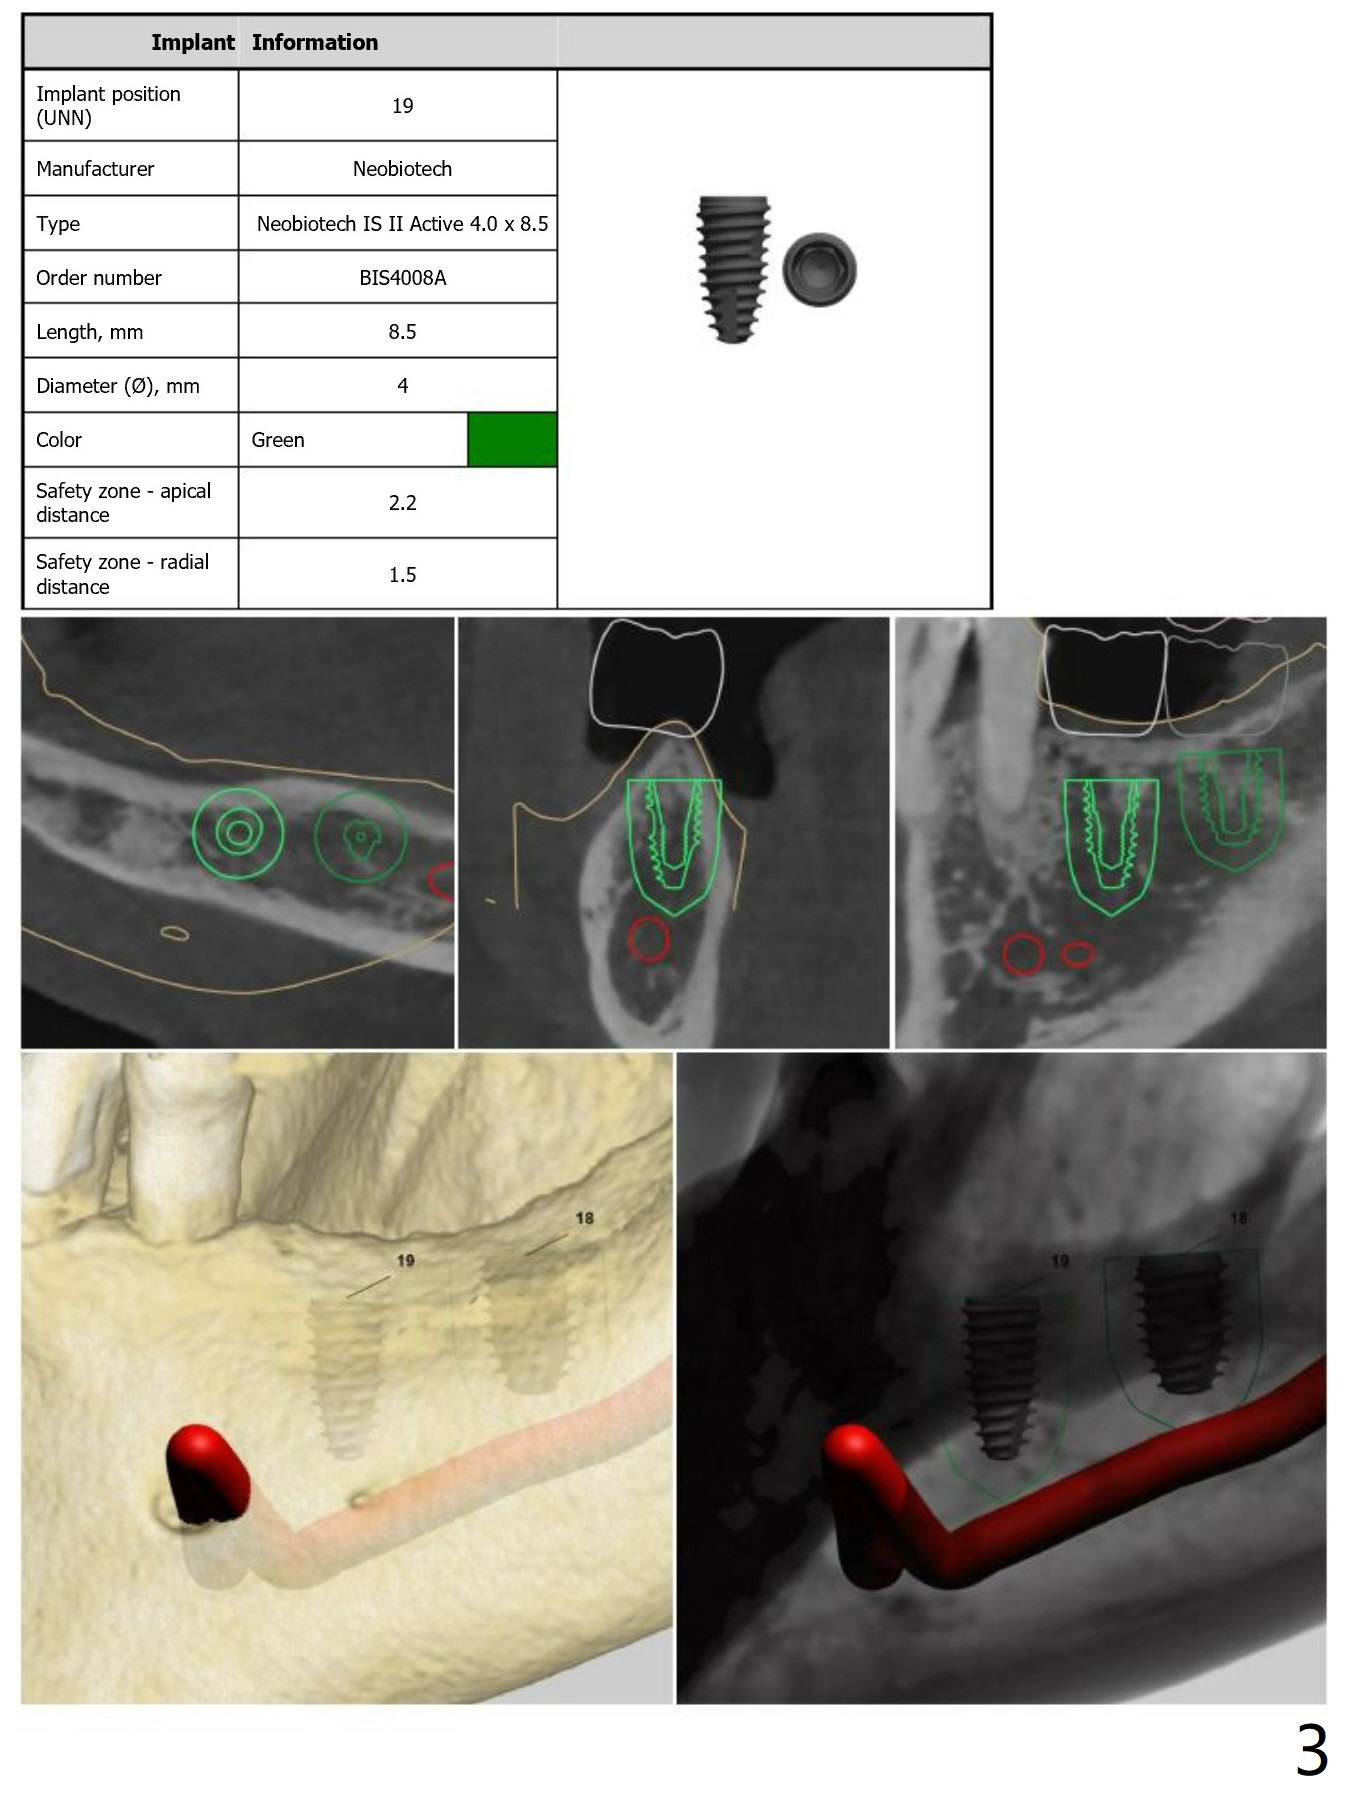

Fixture Anchor Pin at #18

Return to Lower Molar Immediate Implant Armaments  Placement